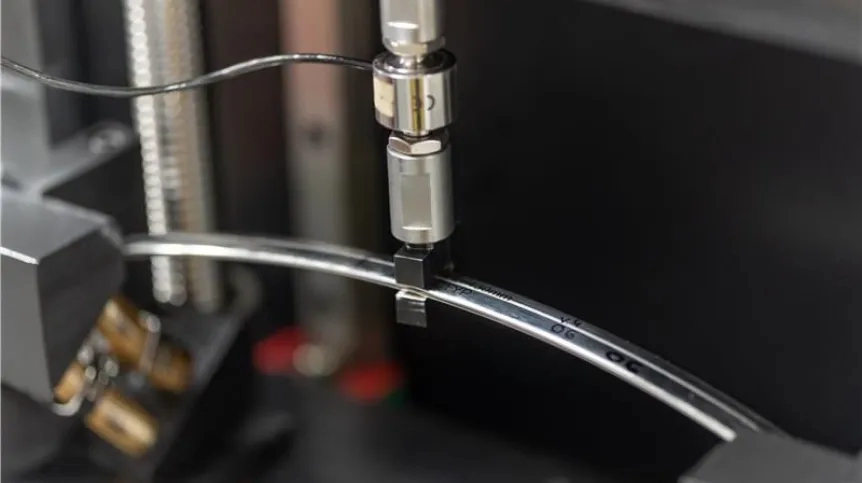

Poznań/Łukasiewicz-PIT testuje nowe implanty dla chorych z wadami klatki piersiowej

Badacze z Łukasiewicz – Poznańskiego Instytutu Technologicznego uczestniczyli w opracowaniu nowych implantów do korygowania klatki piersiowej. Obecnie je testują . Dzięki temu rozwiązaniu osoby z deformacjami klatki piersiowej mogą liczyć na szybszą korekcję i na bardziej komfortowe życie.